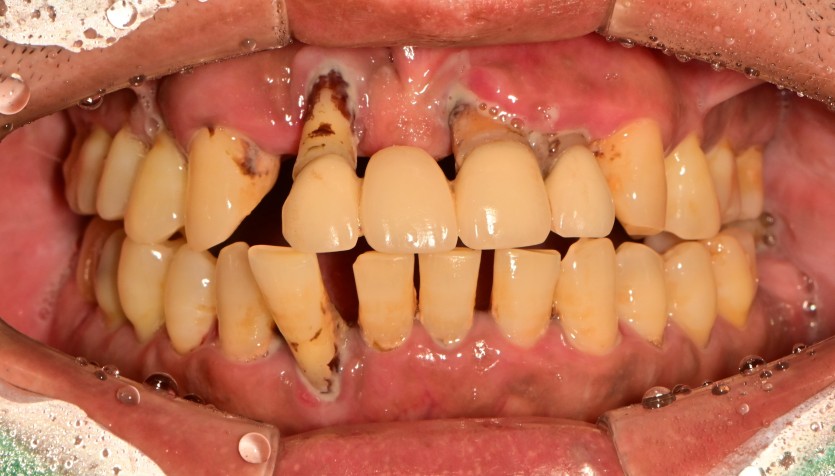

상악 전체 임플란트 증례입니다.(하악 일부)

14개의 임플란트로 완성하였습니다.